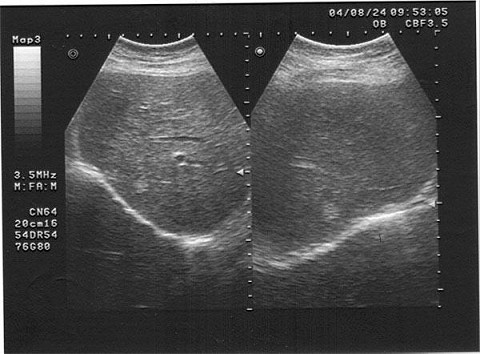

女,40岁,有时右上腹隐痛2年余。结合超声声像图,最可能的诊断为()

A.肝血管瘤

B.肝脓肿

C.小肝癌

D.转移性肝癌

E.肝囊肿

[单选题]女,40岁,有时右上腹隐痛2年余。结合超声声像图,最可能的诊断为()A .肝血管瘤B .肝脓肿C .小肝癌D .转移性肝癌E .肝囊肿